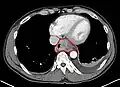

Additional testing is needed to assess how much the cancer has spread (see § Staging, below). Computed tomography (CT) of the chest, abdomen and pelvis can evaluate whether the cancer has spread to adjacent tissues or distant organs (especially liver and lymph nodes). The sensitivity of a CT scan is limited by its ability to detect masses (e.g. enlarged lymph nodes or involved organs) generally larger than 1 cm.[44][45] Positron emission tomography is also used to estimate the extent of the disease and is regarded as more precise than CT alone.[46] PET/MR as a novel modality has shown promising results in preoperative staging with fair feasibility and good correlation in comparison to PET/CT. It can enhance tissue differentiation with lowering the radiation dose to the patient.[47] Esophageal endoscopic ultrasound can provide staging information regarding the level of tumor invasion, and possible spread to regional lymph nodes.

Endoscopy and radial endoscopic ultrasound images of a submucosal tumor in the central portion of the esophagus- Contrast CT scan showing an esophageal tumor (axial view)

- Contrast CT scan showing an esophageal tumor (coronal view)